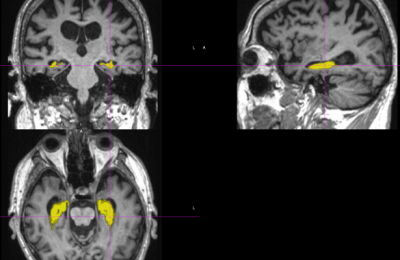

Задумывались ли вы, почему некоторые могут безбоязненно взобраться на Эльбрус или пройти по тонкому дереву, соединяющему два берега горной речки, а другие не могут без страха подняться на девятый этаж на лифте? В недавнем исследовании ученые обнаружили, что ключевую роль в этом играет группа клеток определенного типа в нашем гиппокампе.

Исследователи из Уппсальского университета в Швеции и Федерального университета Риу-Гранди-ду-Норти в Бразилии установили зависимость между клетками определенного типа в гиппокампе и тревожностью человека и, как следствие, его склонностью к риску. Их работа вышла в журнале Nature Communications.

Известно, что даже братья и сестры могут демонстрировать различное поведение в ситуациях, угрожающих безопасности и здоровью. Чтобы узнать, какие процессы в головном мозге различаются у людей с разной склонностью к риску и степенью тревожности, ученые стимулировали некоторые зоны мозга. Выяснилось, что при стимулировании группы OLM-нейронов в гиппокампе регистрируются ритмы головного мозга, характерные для состояния, когда животное или человек чувствует себя спокойно в присутствии опасности. Таким образом, можно регулировать тревожное состояние человека, манипулируя с OLM-нейронами.